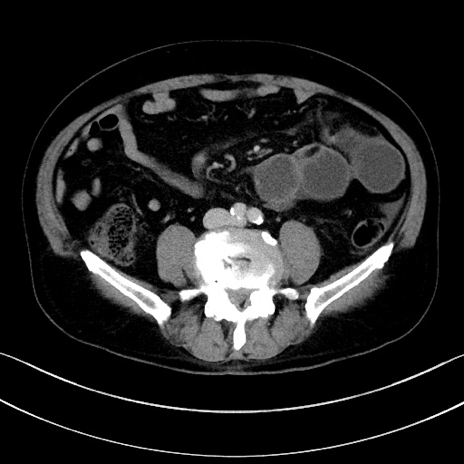

冠状断像

【症例】70歳代男性

【主訴】腹痛

【現病歴】今朝から腹痛あり。全体的に痛い。特に左上の方。排ガスが今日はない。冷や汗が出る。

【既往歴】直腸癌術後

【身体所見】左側腹部〜上腹部に圧痛あり。腹膜刺激症状明らかなではない。軽度反跳痛。左下腹部に術後瘢痕あり。

【データ】WBC 7700、CRP 0.02